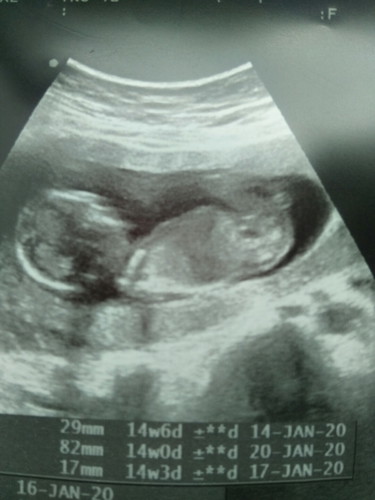

14วีค

ได้ซาวครั้งแรกแล้วค่ะ ไม่ได้ถามหมอว่าเพศอะไร แต่กลับบ้านมาดู เรามองว่าน่าจะชาย แม่ท่านอื่นเห็นด้วยไหมคะ

ท่านี้ดูไม่ออกค่ะคุณแม่ อีกอย่าง 14w น้องยังเล็กเกินไปที่จะระบุเพศได้แน่ชัดนะคะ^^

14 วีคยังไม่ชัวค่ะ อวัยเพศยังไม่สมบูรณ์